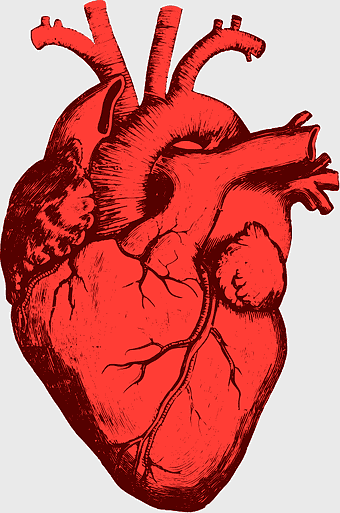

red heart anatomy, human heart drawing, cartoon heart illustration, love and biology, cardiovascular system diagram, medical art depiction, organ structure visualization -

human heart anatomy, red heart illustration, heart organ diagram, heart muscles and valves, cardiovascular system diagram, human body organ chart, anatomical heart structure -

human heart illustration, cardiac anatomy diagram, heart blood vessels, medical organ visuals, cardiovascular system chart, human anatomy study, circulatory system illustration -

human heart anatomy illustration, watercolor heart painting, heart shape medical care, red heart organ, cardiovascular system diagram, anatomical heart drawing, heart structure analysis -